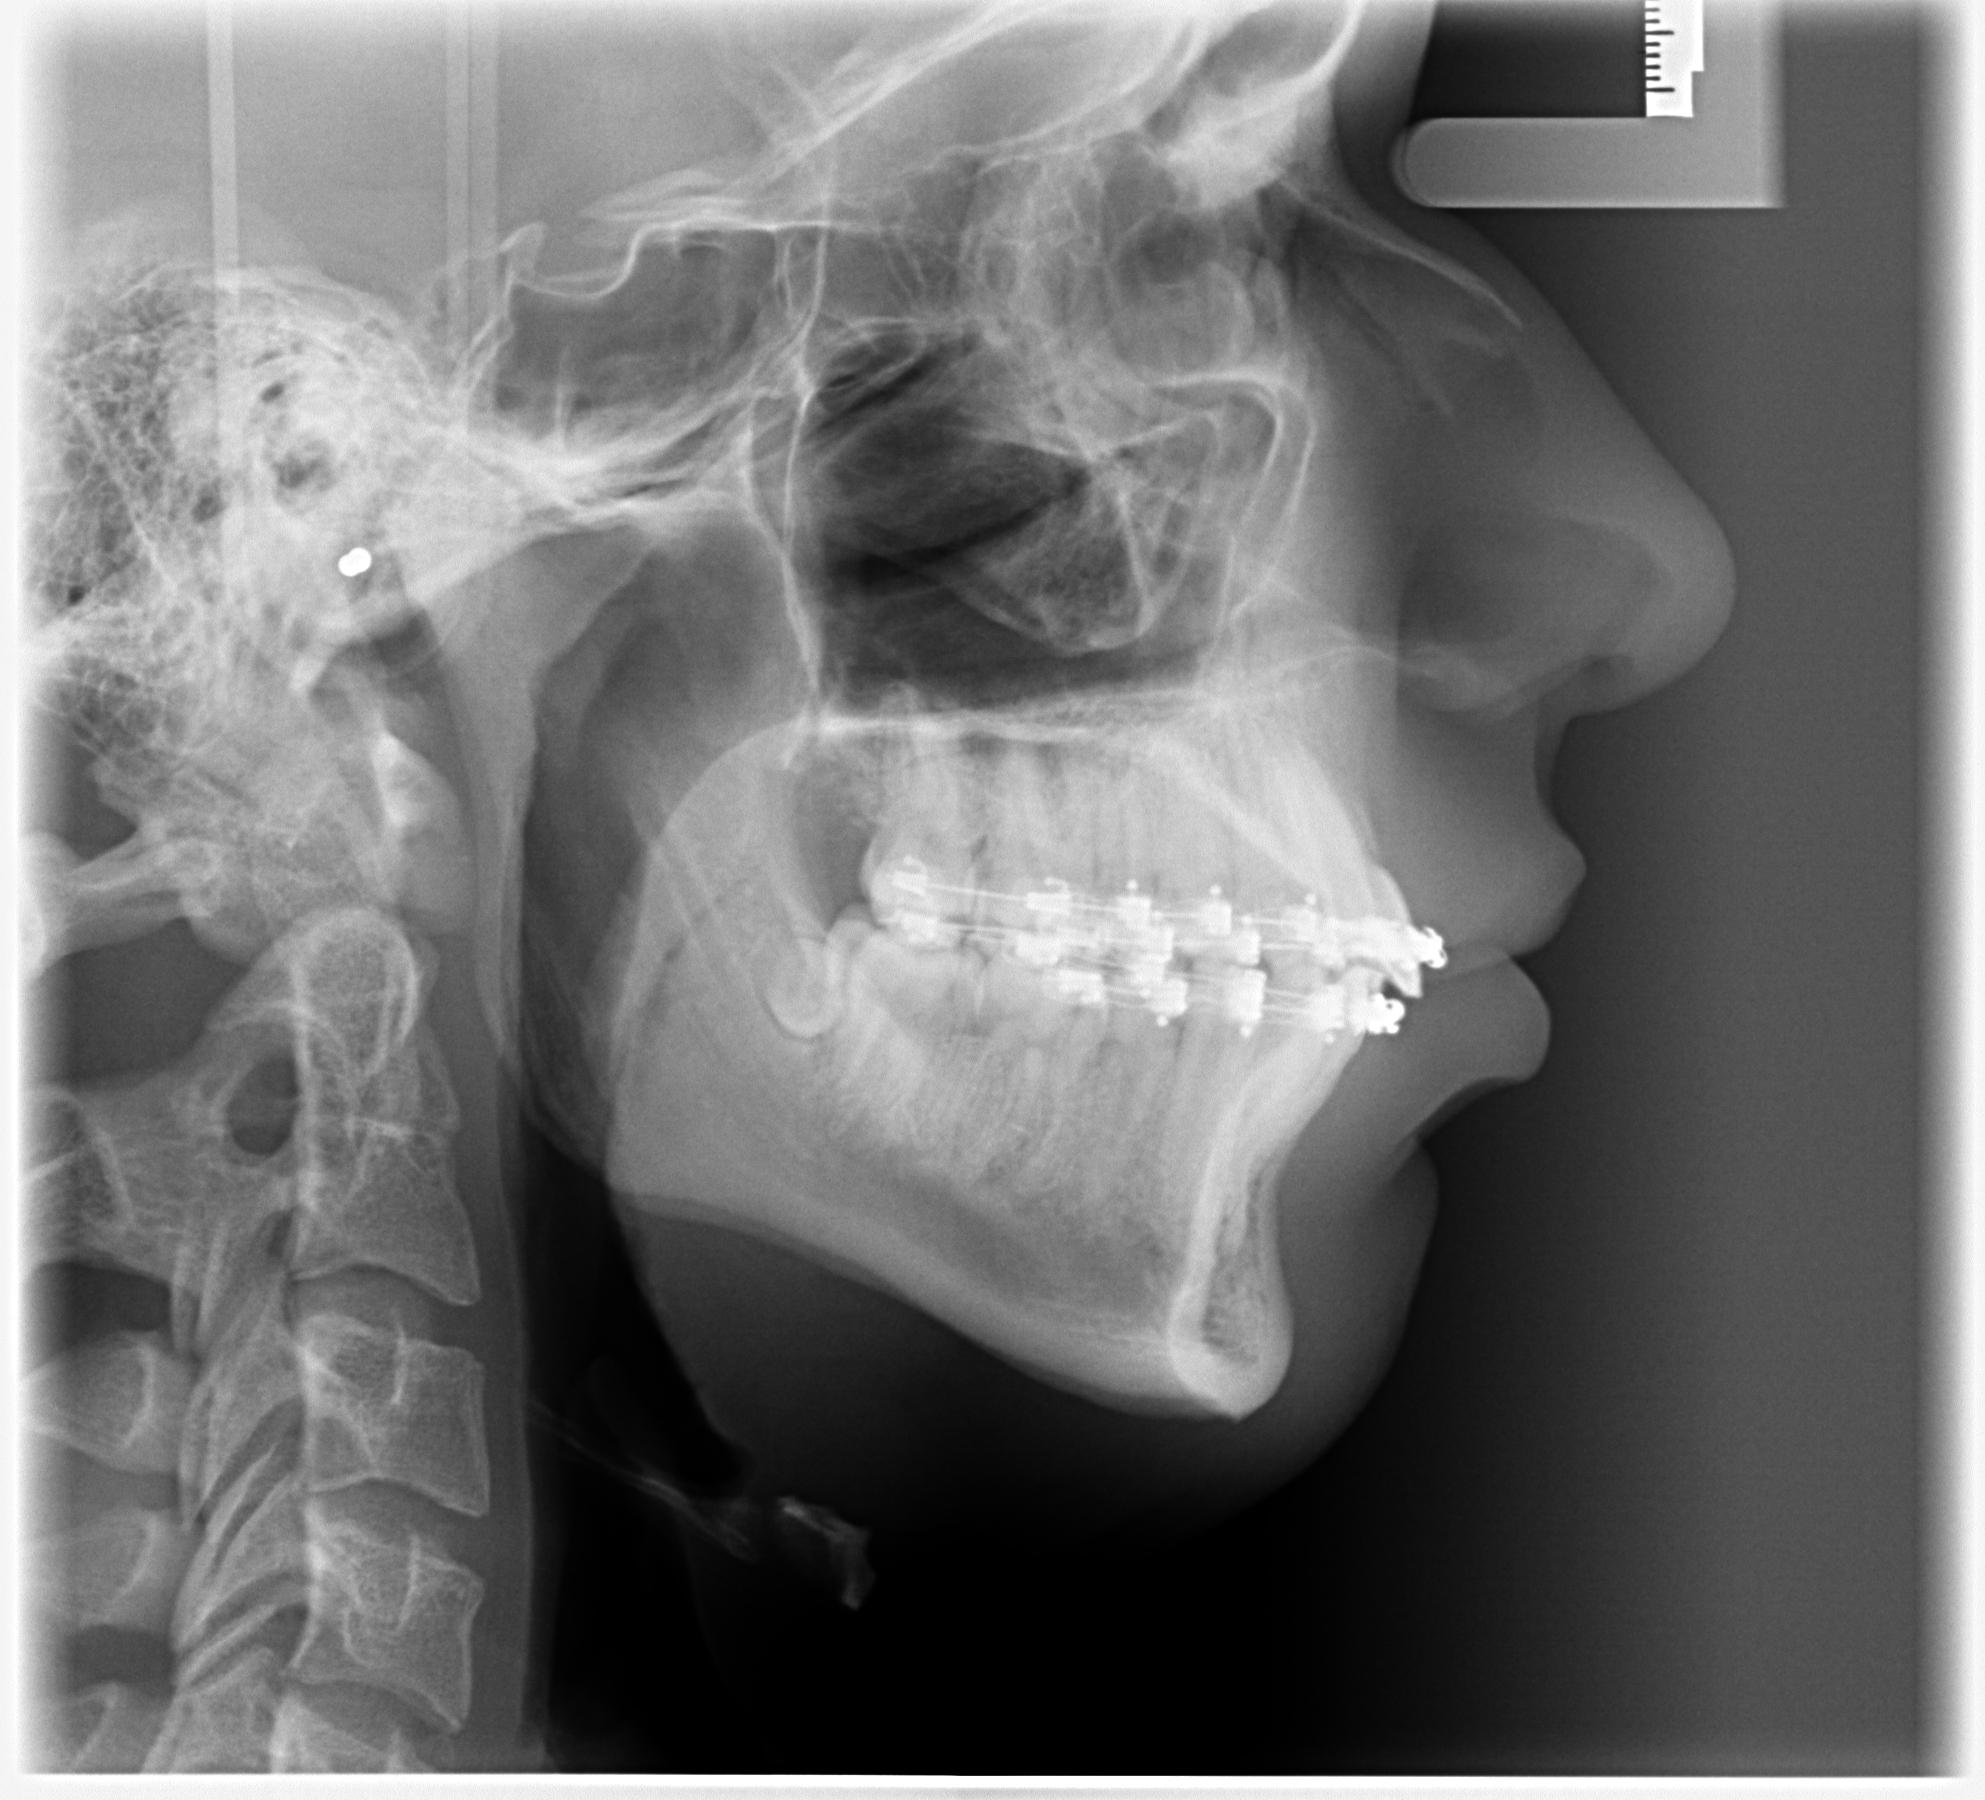

I had Bimaxsurgery + genioplasty yesterday performed by Dr Dr Kater, Frankfurt am Main, Germany. I'm 17 and it went well, no nerves are botched and he told me the Plan was executed perfectly fine. In the pictures you can see 24h before and 24h after the surgery. He did a great job with my maxilla and mandible but the genioplasty is slightly underadvanced. My nose had a very big glowup but it'll all look different in 5 months i'm very bloated rn. What do yall think?

Mirin, ur nose bump is already gone I also have similar case like u and also have short face syndrome but am confuse if getting CW rotation will make me more recessed, in ur x ray i can see u wont have a major change in ur face apart from ur nose bump, ramus and chin , i think u will need more osteotomy to get the perfect length of the bone just like LL surgery where they increase ur bone length everyday. Honestly am not aware abt this i will have to research myself abt that cuz gettin a CW rotation will do more harm to face than good it make ur face long and recessed

i had a very very very minimal cw, not optimal for forward growth but there's hardly any surgeon in germany that does cw and i had short face syndrome so it would't ascend me that much. my nose lips and chin look far better i can already see my ramus through the swelling, i'm very happy, but youre right: I didn't get that much sagittal movement, still a good bimax tho

this is my side now (8 days later) btw

this is before